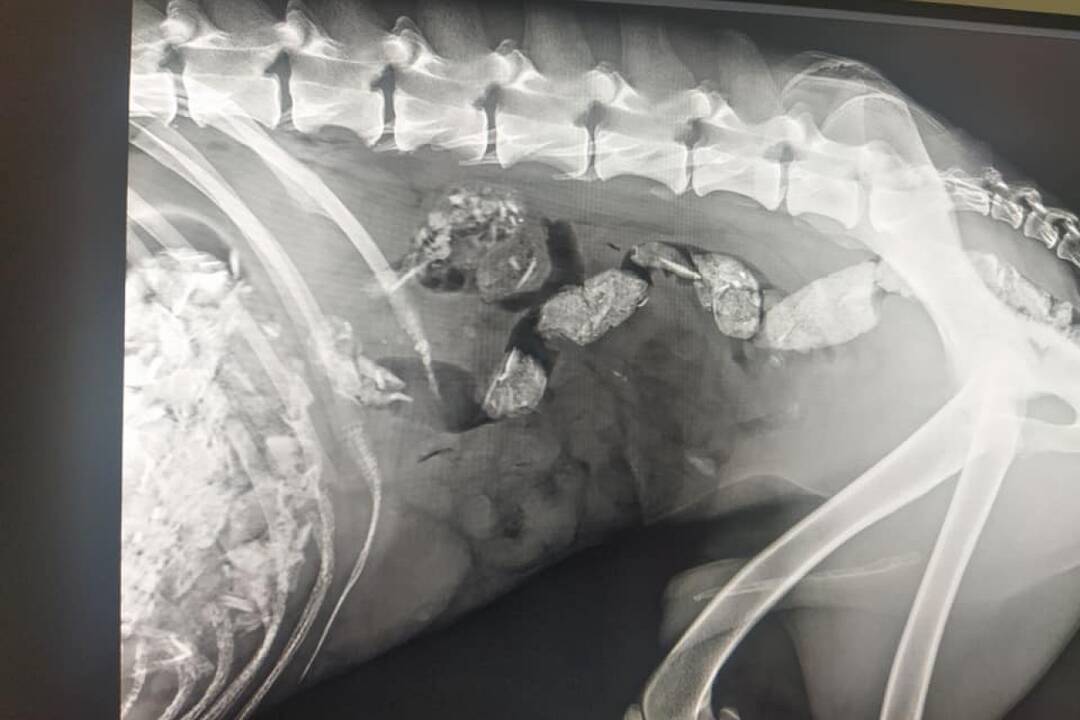

FOTO: Utýraný a vyhladovaný Odin mal v tele starší brok

FOTO: Utýraný a vyhladovaný Odin mal v tele starší brok, foto 6

Zdroj: Facebook/Sloboda zvierat